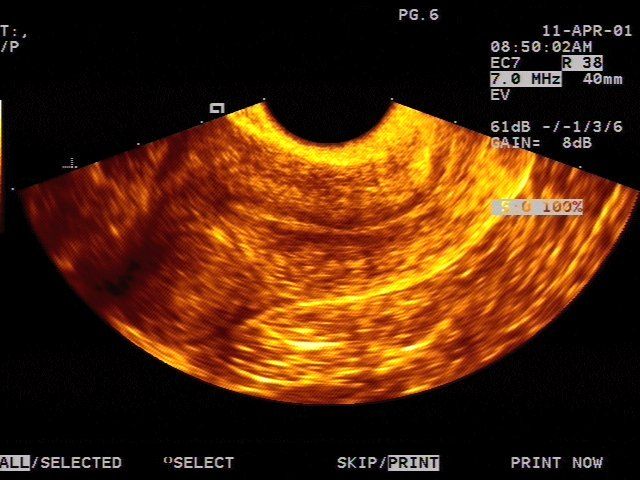

This is a confirmed case of scar ectopic pregnancy. Yesterday, I carried out this exam in an emergency room, without much time to perform an adequate sonogram, the patient did not feel good with “cramps” but no signs of bleeding.